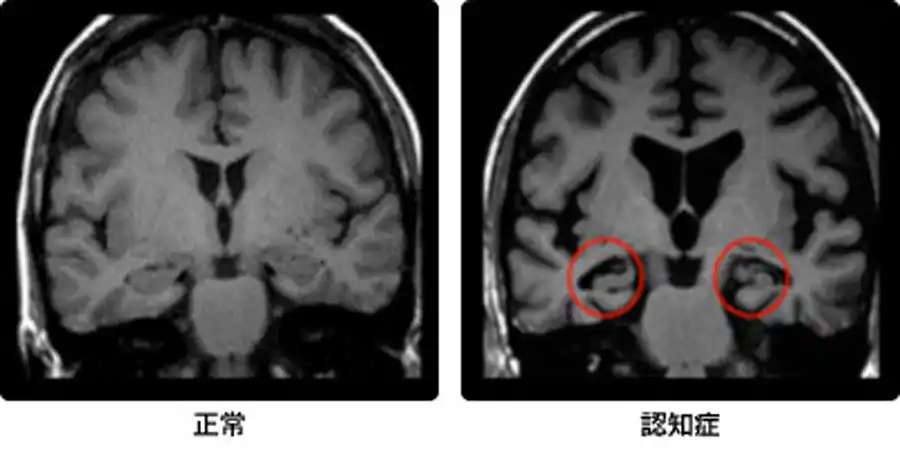

最近では、造影剤を用いて濃度や信号の経時的変化から脳循環を解析する検査法(MRパフュージョン)やMRIでの認知症検査(VSRAD)も増えつつあります。

VSRADとは、早期アルツハイマー型認知症診断支援システムの略語で、人の記憶に関する役目を果たす海馬の萎縮程度を評価するMRI画像処理、解析ソフトのことを言います。

認知症の画像を見ると、左の正常より黒い隙間が目立ち、脳が萎縮していることが分かります。

早期で軽度の萎縮の場合、通常のMRI検査では評価が難しいとされていました。VSRADでは脳の中でも記憶を担当する海馬がどの程度萎縮しているか、%表示し、萎縮程度をカラー表示することによって、軽度の萎縮も評価しやすくし、認知症の早期診断を補助することができます。